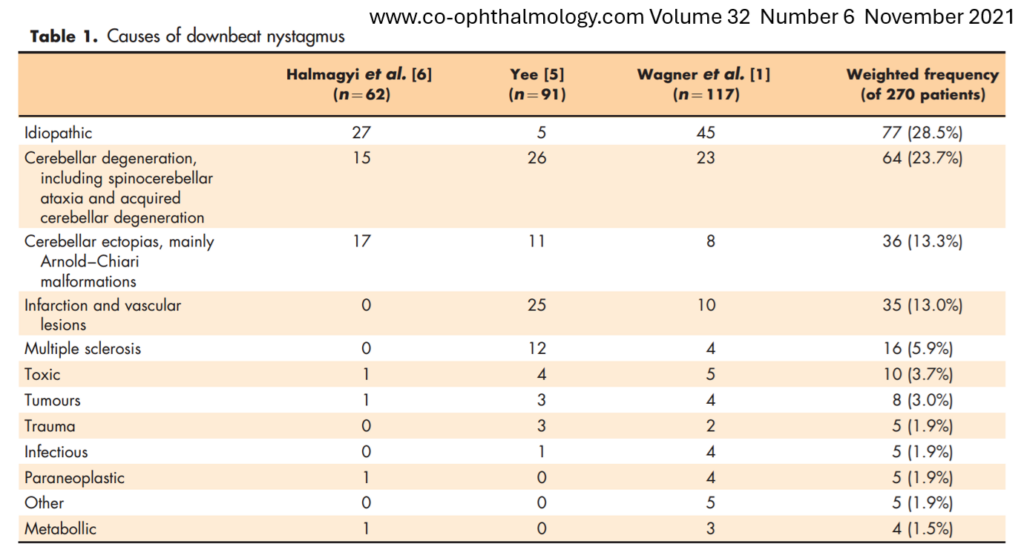

Com relação a causa do NEVI, nesse trabalho abaixo, combinaram três séries de pacientes com NEVI. Observem que há uma alta proporção de causa idiopática. Porém, cerca de 40% dos pacientes apresentaram uma explicação estrutural evidente, indicando a importância dos exames de neuroimagem.

Nesse mesmo artigo, é proposto uma classificação do NEVI em dois grandes grupos. O causado por uma patologia estrutural evidente e os de causa não estrutural.

Nesse caso, os exames de imagem não ajudaram na identificação do fator causal.